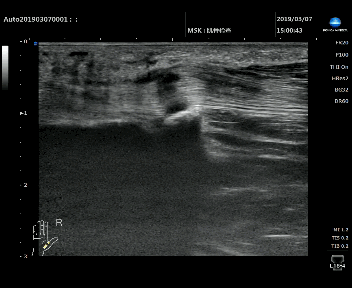

狹窄性腱鞘炎的肌腱動態掃查

■ 肌腱與腱鞘之間滑動消失